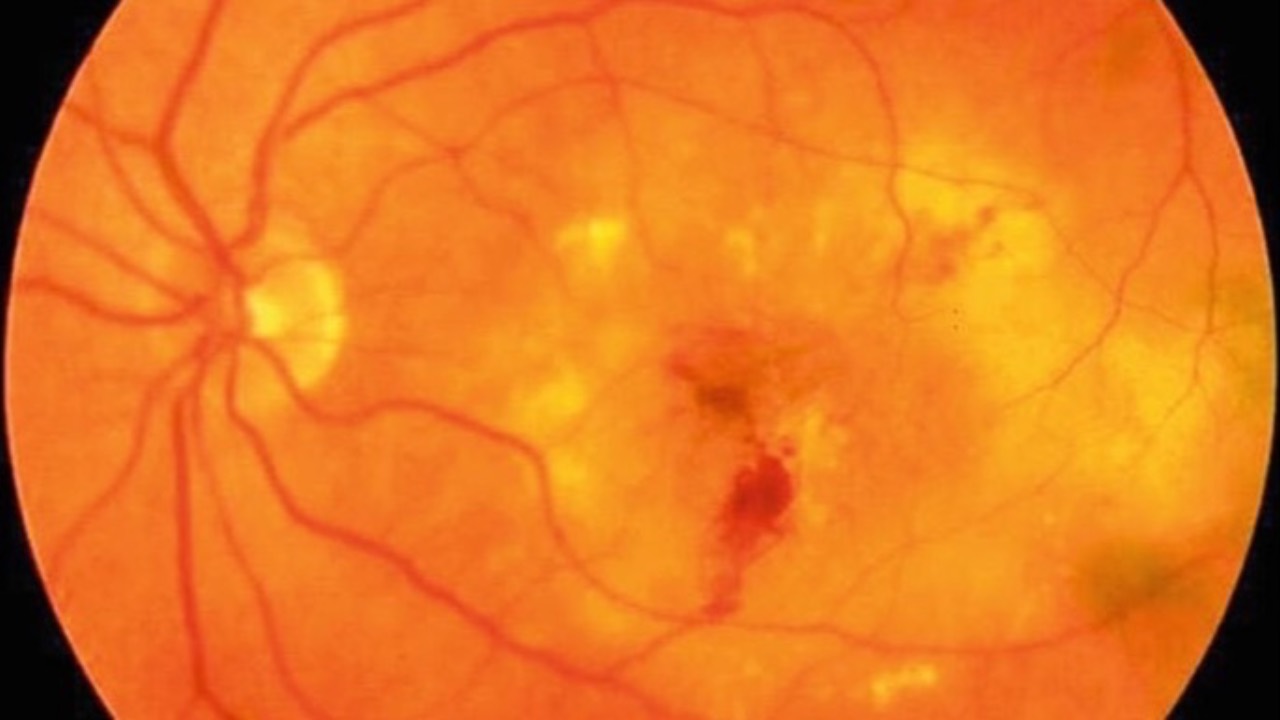

Purtscher-Like Retinopathy with Systemic Lupus Erythematosus

BMC Ophthalmology recently published a case of a 25-year-old patient who presented with sudden bilateral vision loss, revealing a rare case of simultaneous bilateral Purtscher-like retinopathy associated with systemic lupus erythematosus (SLE).

Exam showed retinal edema, artery narrowing, and s...